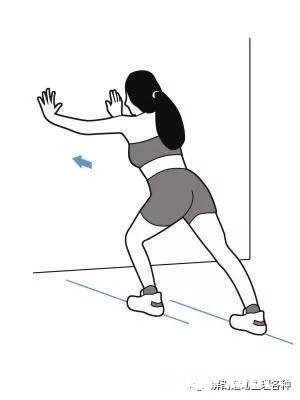

3.避免运动后拉伸

运动后大家都习惯了做拉伸动作,但是这无形之中又加剧了足底筋膜炎的发生 。

尤其是跟腱很紧的朋友,做这个拉伸动作时,后跟不能着地,结果越拉越严重 。